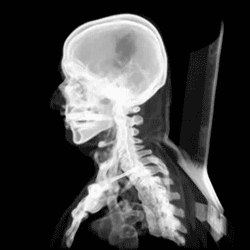

Injuries and treatment

Injuries to the brain can be life-threatening. Normally the skull protects the brain from damage through its high resistance to deformation; the skull is one of the least deformable structures found in nature, needing the force of about 1 ton to reduce its diameter by 1 cm.[20] In some cases of head injury, however, there can be raised intracranial pressure through mechanisms such as a subdural haematoma. In these cases, the raised intracranial pressure can cause herniation of the brain out of the foramen magnum ("coning") because there is no space for the brain to expand; this can result in significant brain damage or death unless an urgent operation is performed to relieve the pressure. This is why patients with concussion must be watched extremely carefully. Repeated concussions can activate the structure of skull bones as the brain's protective covering.[21]

Dating back to Neolithic times, a skull operation called trepanning was sometimes performed. This involved drilling a burr hole in the cranium. Examination of skulls from this period reveals that the patients sometimes survived for many years afterward. It seems likely that trepanning was also performed purely for ritualistic or religious reasons. Nowadays this procedure is still used but is normally called a craniectomy.

In March 2013, for the first time in the U.S., researchers replaced a large percentage of a patient's skull with a precision, 3D-printed polymer implant.[22] About 9 months later, the first complete cranium replacement with a 3D-printed plastic insert was performed on a Dutch woman. She had been suffering from hyperostosis, which increased the thickness of her skull and compressed her brain.[23]

A study conducted in 2018 by the researchers of Harvard Medical School in Boston, funded by National Institutes of Health (NIH), suggested that instead of travelling via blood, there are "tiny channels" in the skull through which the immune cells combined with the bone marrow reach the areas of inflammation after an injury to the brain tissues.[24]